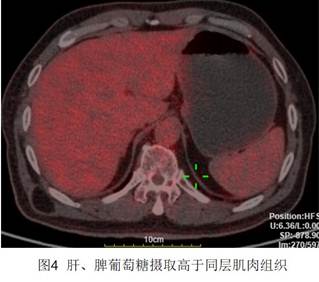

4、肝臟、脾臟。正常情況下,肝、脾都會出現(xiàn)一定程度的18F-FDG生理性攝?。▓D4),脾臟放射性水平低于肝臟。